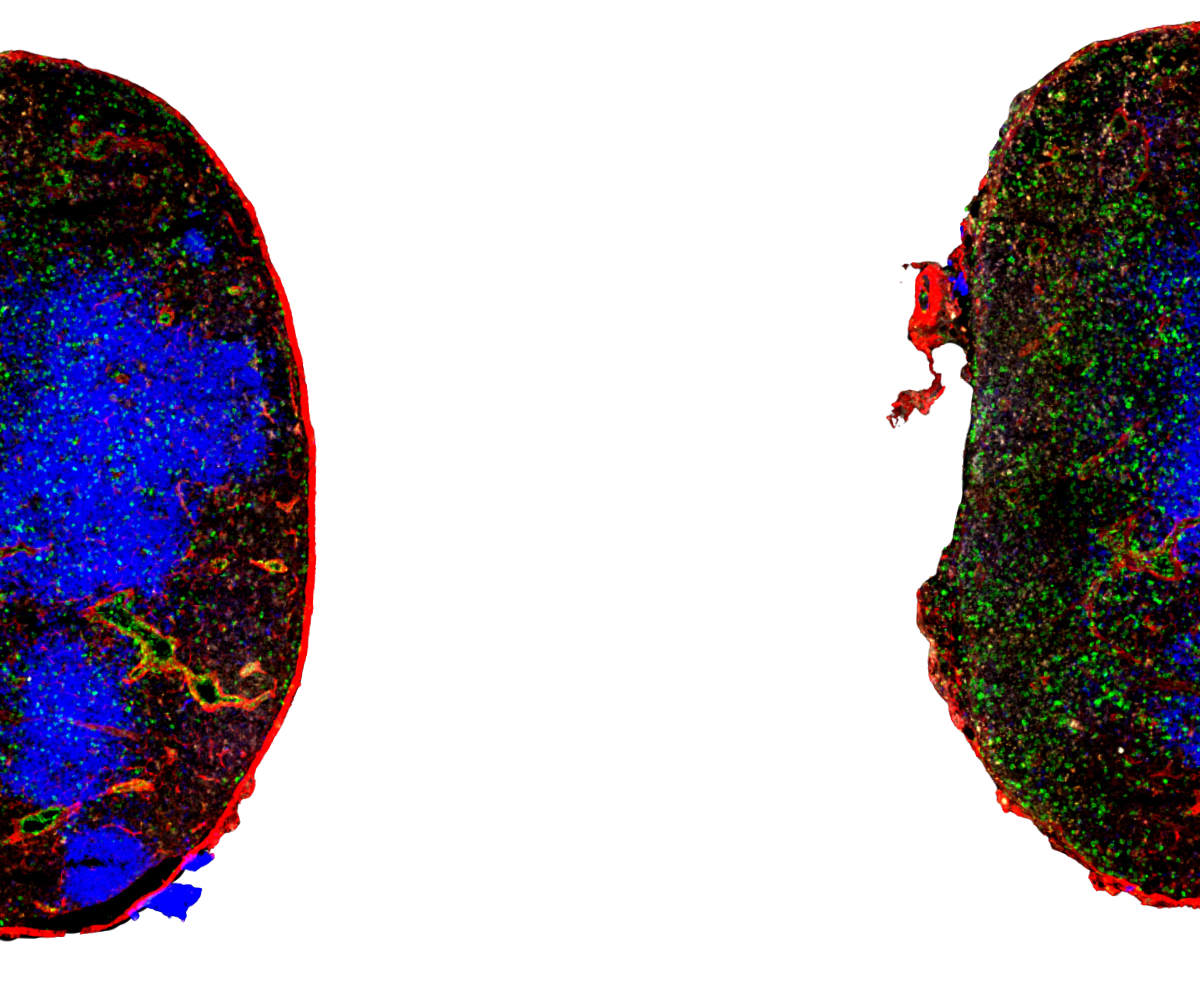

Raul M. Torres, PhD, Professor of Immunology and Microbiology, and Kimberly N. Kremer, Senior Instructor of Immunology and Microbiology, are corresponding authors of an original research article published January 16 by Frontiers in Immunology that shows liver sinusoidal endothelial cells regulate the balance between hepatic immunosuppression and immunosurveillance. Ten co-authors are from our campus.